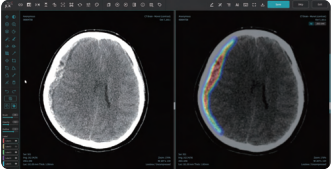

[로이슈 전여송 기자] 의료 AI 1호 상장기업 제이엘케이(대표 김동민)가 올해 본격적인 미국 진출 계획의 일환으로 현지에서 수요가 많은 CT영상 기반 뇌 경막하 출혈 분석 솔루션 JLK-SDH를 새롭게 출시하며 뇌출혈 진단에 필요한 CT기반 AI 솔루션의 세분화 및 전문성이 강화된 제품 라인업을 완료했다고 29일 밝혔다.

JLK-SDH는 뇌를 둘러싸고 있는 경막 내부 혈관의 파열로 인한 출혈을 진단할 수 있는 솔루션으로 주로 낙상이나 교통사고 등 외상으로 인해 발생하는 경막하 출혈 환자의 신속하고 정확한 병변 분석을 위해 개발됐다. 일반적으로 경막하 출혈 환자는 두부 외상으로 응급실로 이송되는 경우가 빈번하기에 가장 먼저 CT 촬영을 진행해 진단을 하고 치료 계획을 수립하게 된다.

기존 출시된 뇌출혈 진단 솔루션인 JLK-ICH가 주로 전반적인 급성 뇌출혈 진단에 강점을 보인 반면 이번에 출시된 JLK-SDH는 CT에서 신호강도가 강하지 않아 정상 뇌와 구분이 어려운 아급성(subacute) 혹은 만성 경막하출혈 데이터 학습에 공을 들여 어려운 뇌출혈 진단에 강점이 있다고 회사 측은 전했다.

사측은 이번에 개발된 JLK-SDH 솔루션이 응급 상황에서 의료진에게 신속하고 정확한 진단을 내리는 데 큰 도움이 될 것이라고 설명했다. 교통사고나 폭행 등 심각한 두부 외상으로 인한 급성 경막하 출혈은 시간과의 싸움이라고 할 수 있을 정도로 빠른 진단과 치료가 절실하다. 응급실에 도착한 환자가 이미 혼수상태에 빠져 있는 경우도 많고 출혈이 지속되면 뇌사상태까지도 이어질 수 있는 만큼 JLK-SDH 솔루션을 통해 골든타임을 확보하는 데도 큰 역할을 할 것으로 기대했다.

제이엘케이는 이번에 선보인 JLK-SDH를 통해 더욱 탄탄한 뇌졸중 CT 솔루션을 구성하게 됐다. 미국 의료기관의 뇌졸중 진단 시 CT 촬영이 많은 것을 착안해 보강된 CT 솔루션으로 미국 시장 진출에 더욱 박차를 가할 계획이다.

제이엘케이 김동민 대표는 "응급 상황에서 빠르고 정확한 진단과 치료가 가능하도록 돕는 JLK-SDH 출시로 제이엘케이는 미국시장 진출에 유용하게 활용될 CT기반의 뇌출혈 솔루션을 모두 갖추게 됐다. 이를 통해 미국 진출이 더욱 탄력을 받게 돼 감회가 새롭다"며 "향후 JLK-SDH의 빠른 FDA 인허가 신청을 위해 집중하고 현지 상황에 맞는 진출 전략을 구상해 빠른 미국 의료시장 선점을 위해 최선의 노력을 다하겠다"고 말했다.